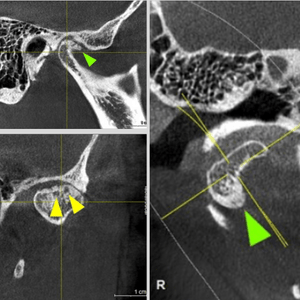

Scanner Cone-Beam CT de última generación

La mejor tecnología alemana

Equipo extraoral

Sirona SL

Panorámicas, teleradiografias y CBCT con el sensor más moderno, preciso y de baja dosis.

2Diagnóstico por especialista

Cada caso es único. Informe completo en el menor tiempo posible.